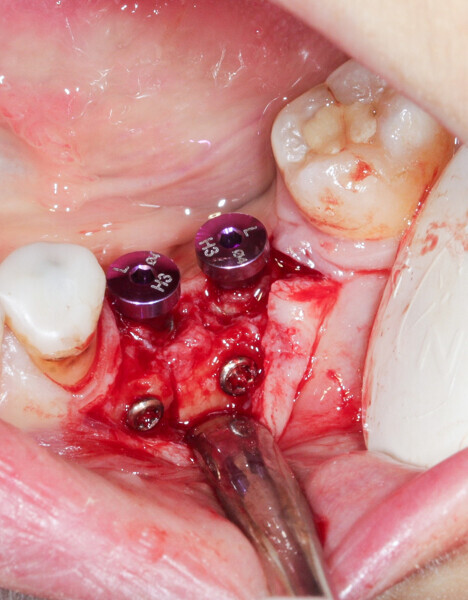

We had three alternative courses of action: a bone block graft from the mandibular ramus,2 a segmental osteotomy4 or a radicular graft, knowing that tooth #46 could not be saved. We chose the third option because it allowed for simultaneous implant placement and bone reconstruction. A large flap was elevated to assess the gap in the bone and in anticipation of closing the flap on an augmented ridge. Two implants were placed as normal despite the low residual bone thickness in the vestibular area of the planned positions for the implants (Fig. 5). The roots of tooth #46 were extracted atraumatically (root separation, use of piezo-surgery, etc.) and were then prepared as described. The roots were shaped to fit the defect and fixated at the insertion site using osteosynthesis screws (Fig. 6).3 The flap was mobilised and stretched to achieve edge-to-edge closure without tension, and a 4/0 rapidly resorbed braided thread was used for the sutures (Fig. 7). Four months after the bone augmentation and implant placement, healing abutments were connected to the implants and the osteosynthesis screws removed (Figs. 8 & 9). During the operation, time was taken to perform a visual check that ankylosis of the radicular grafts had been successful and that these were sound. Finally, a CBCT assessment was performed. The prosthesis was fitted by our colleague a few weeks later, once the soft tissue had healed.